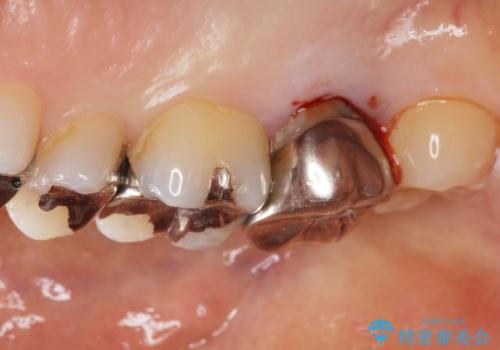

- 奥歯に違和感があることを主訴に来院された患者様です。

精査したところ、右上の奥歯(右上7)はう蝕が深く骨吸収も進行しており保存不可能な状態でした。

金属アレルギーの疑いがあり、インプラントも避けたいとの患者様のご希望により、親知らずを移植することにしました。